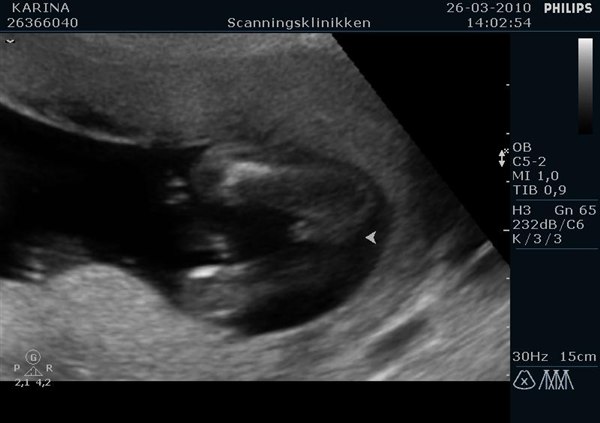

Men det der ligger i det, er at kønnet er udviklet, men at man på scanningen ikke kan kende forskel, medmindre barnet ligger helt perfekt, og så skal man være ekstrem erfaren for at se forskel, da skamlæber og pung ligner hinanden.

Så ja, man kan godt, men chancen for at den lille ligger rigtigt og at de har ret i hvad de tror de ser, er meget lille.